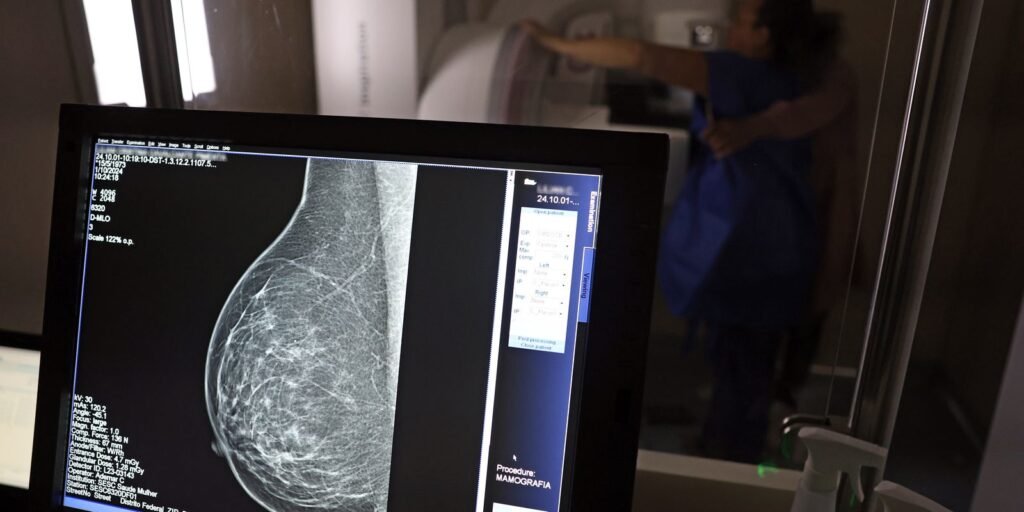

O Ministério da Saúde passou a recomendar o acesso a mamografia, via Sistema Único de Saúde (SUS), para mulheres de 40 a 49 anos – mesmo que não haja sinais ou sintomas de câncer de mama. De acordo com a pasta, a faixa etária concentra 23% dos casos da doença, e a detecção precoce aumenta as chances de cura.

A medida faz parte de um conjunto de ações anunciadas nesta terça-feira (23) voltado para a melhoria do diagnóstico e da assistência. A recomendação para mulheres a partir dos 40 anos é que o exame seja feito sob demanda, em decisão conjunta com o profissional de saúde.

As mamografias via SUS em pacientes com menos de 50 anos, de acordo com a pasta, representam 30% do total, o equivalente a mais de 1 milhão apenas no ano de 2024.

Outra medida anunciada é a ampliação da faixa etária para o rastreamento ativo – quando a mamografia é solicitada de forma preventiva a cada dois anos. A idade limite, até então, era 69 anos. Agora, passa a ser 74 anos. Dados do ministério revelam que quase 60% dos casos de câncer de mama estão concentrados entre 50 e 74 anos.

“A ampliação do acesso à mamografia aproxima o Brasil de práticas internacionais, como as adotadas na Austrália, e reforça o compromisso em garantir diagnóstico precoce e cuidado integral às mulheres brasileiras. O câncer de mama é o mais comum e o que mais mata mulheres, com 37 mil casos por ano”, reforçou a pasta.

Os números mostram que, em 2024, cerca de 4 milhões de mamografias para rastreamento e 376,7 mil exames diagnósticos foram realizados no SUS.